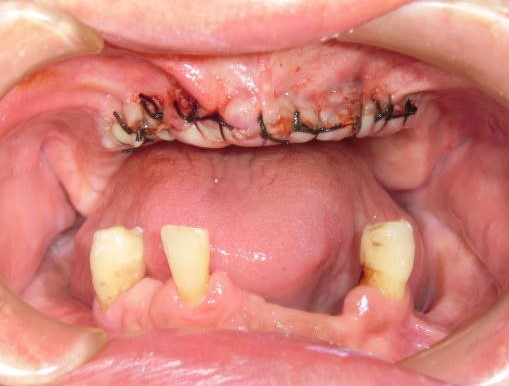

症例1:67歳男性

総義歯が安定しないため、義歯性線維腫の切除を行いました。

25分かかりましたが、その後の入れ歯の安定は大きく改善しました。

外科的切除がおこなわれます。